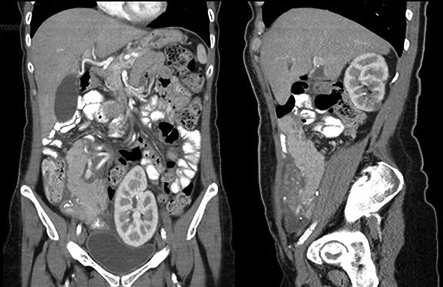

Fig. 5. TC post operatoria: cortes coronales y sagitales.

Los valores de glucemia (210 mg/ dl), amilasa (460 U/L) y lipasa (270 U/L) aumentados post cirugía, además del dolor abdominal y distensión que presentaba la paciente, motivaron la indicación de una TCMD con contraste EV post operatoria (Fig. 5).

En el caso Nº 1, la TC mostró presencia de líquido y alteración de la grasa peripancreática del órgano trasplantado, como así también líquido en los recesos pelvianos, característico de pancreatitis. La evolución clínica y la correlación con el laboratorio clínico confirmaron estos hallazgos. Como tratamiento se indicó reposo digestivo, observándose en los 10 días posteriores a la tomografía considerable mejora clínica y disminución de los valores de laboratorio. Se dio el alta al paciente con una glucemia de 76 mg/dl y una creatinina de 1.1 mg/dl.